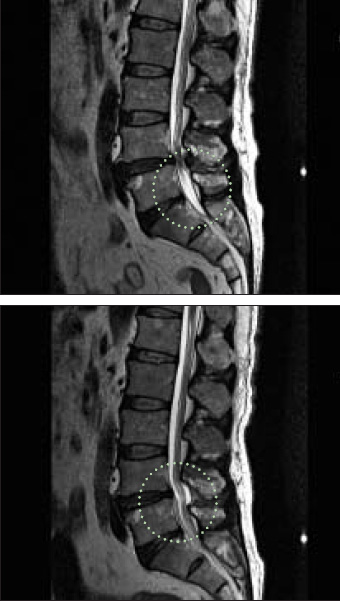

4·5번 요추에 협착증이 생긴 모습(위)과 단일통로 협착증 내시경 시술 후 협착이 있던 부위 신경관이 확장된 모습(아래)./다나은신경외과 제공

최근에는 고령자들의 척추관 협착증 치료 효과와 안전성을 높이기 위한 다양한 치료법이 개발되고 있다. 그중 하나가 '단일통로 협착증 내시경 시술'이다. 단일통로 협착증 내시경 시술은 말 그대로 피부에 하나의 구멍을 뚫은 뒤, 해당 부위에 내시경 기구를 넣어 신경을 누르고 있는 부위를 제거하는 시술이다. 내시경 기구 안에는 총 3개의 작은 통로가 있는데, 각각의 통로에는 환부를 볼 수 있는 내시경 렌즈와 시술 과정에서 발생한 인대 조각 등을 체외로 배출하도록 하는 생리식염수, 인대 제거를 위한 기구가 들어있다.